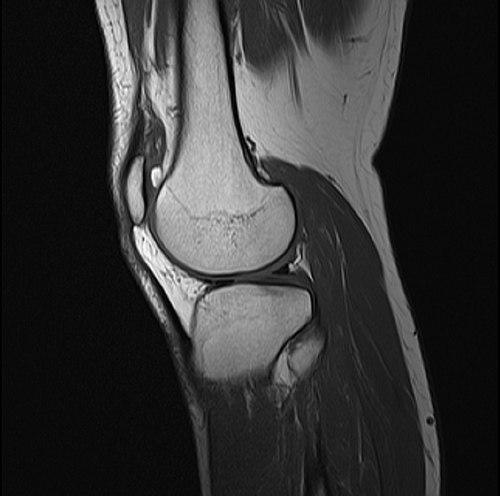

Normal knee phantom with intact bone, cartilage, menisci, and ligaments for baseline comparison

Knee with complete ACL rupture showing torn ligament, bone bruises on lateral femoral condyle and posterolateral...

Knee with medial meniscus tear (bucket-handle type) showing displaced meniscal fragment, joint effusion, and...

Degenerative knee with joint space narrowing, osteophytes, subchondral sclerosis, cartilage thinning, and Baker's cyst